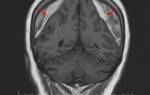

В сложных случаях лечение может потребовать хирургического вмешательства. Для оценки необходимости операции проводят магнитно-резонансную томографию или ультразвуковое исследование. Во время операции на месте повреждения делают небольшой надрез и удаляют кровяные сгустки путём выдавливания.

Лечение внутренней гематомы на ноге

Местоположение внутренней гематомы — мышцы и подкожная клетчатка. Кровоизлияние в травмированной зоне ноги вызывает боль, припухлость, изменение цвета кожи, нарушение функции мышц и иногда повышение температуры.

Лечение внутренней гематомы на ноге включает удаление крови методом пункции. Если есть кровоточащий сосуд, гематому вскрывают, эвакуируют кровь и восстанавливают целостность поврежденного сосуда. В некоторых случаях необходимо дренирование гематомы.